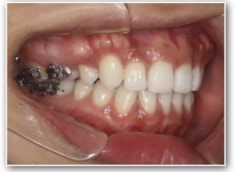

治療前